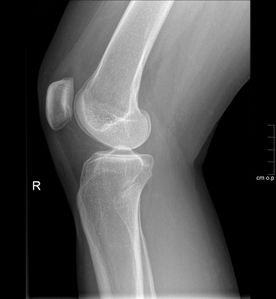

• Alle Röntgenaufnahmen des Skelettes inklusive orthopädische Spezialaufnahmen

• Aufnahmen nach Verletzungen